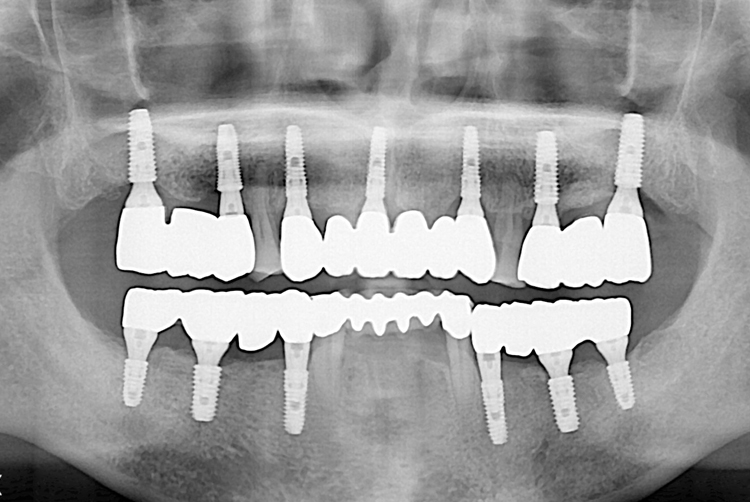

[임플란트] 임플란트

1497 윤종길_후.jpg

치료후 : 2019-06-27

세종치과는 많은 환자와 다양한 케이스를 바탕으로 항상 편안한 임플란트 수술을 제공하고자 노력하고,

오래동안 튼튼히 쓸 수 있는 임플란트 수술을 가장 큰 목표로 삼고 있습니다